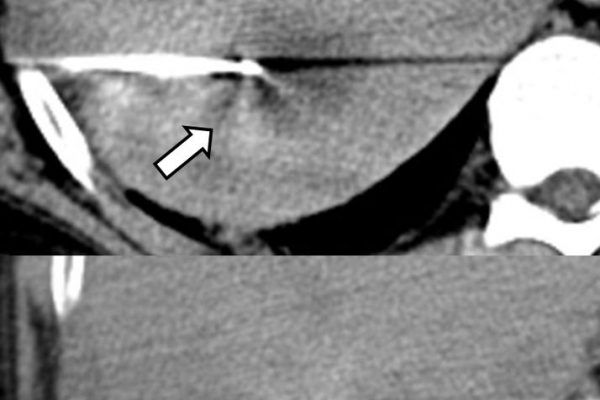

Πρόκειται για την πιο σύγχρονη τοπική θεραπεία όγκων του ήπατος, του νεφρού, του πνεύμονα, των οστών και των όγκων μαλακών μορίων. Παθοφυσιολογικά βασίζεται στην τοπική καταστροφή των καρκινικών κυττάρων με τη δημιουργία ιδιαίτερα υψηλών θερμοκρασιών εντός του όγκου. Αυτό επιτυγχάνεται με τοποθέτηση ειδικών ηλεκτροδίων εντός του όγκου υπό ακτινολογική καθοδήγηση (αξονικός τομογράφος ή υπέρηχος). Τα ηλεκτρόδια αυτά παράγουν υψηλή θερμοκρασία είτε με τη βοήθεια ραδιοσυχνοτήτων (RFablation), είτε με τη βοήθεια μικροκυμάτων (MWablation) και προκαλούν πηκτική νέκρωση των καρκινικών κυττάρων χωρίς να επηρεάζουν τα φυσιολογικά κύτταρα.Το αποτέλεσμα είναι μόνιμο.